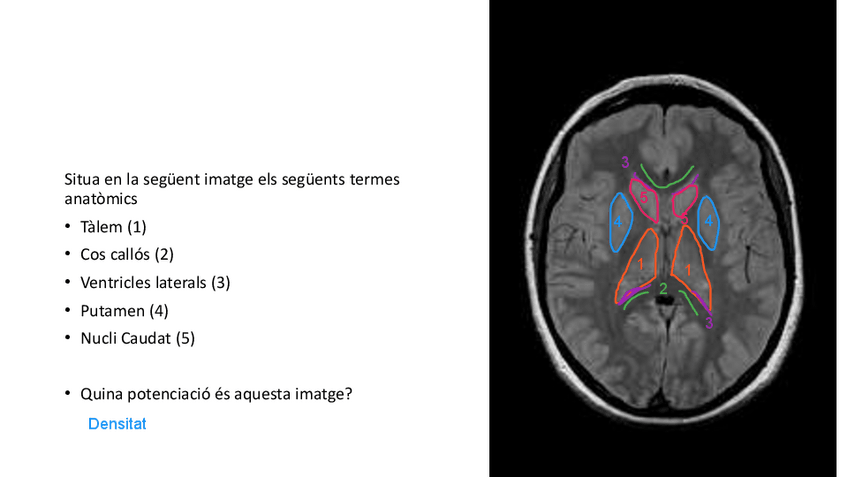

He publicado nuevos apuntes de Técnicas de Imagen por Resonancia Magnética: RESUM-sequencies-ressonancia.pdf

Imatges de resonancia amb les seves parts localitzades amb colors.

4 páginas